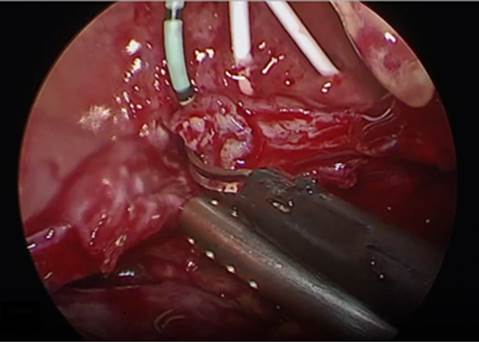

5. Movilización y disección vesical. Se incide vejiga de forma vertical por debajo de la reflexión de globo vesical (Fig. 7) y se localiza el catéter del trayecto fistulosos, así como catéteres ureterales.

6. Reparación de la fístula. Se diseca la pared posterior de la vejiga de la pared anterior de la vagina con disección roma o cortante. Se procede a realizar fistulectomía circunferencial con corte frío (Fig. 8), se completa disección y separación de pared vaginal de la vesical (Fig. 9).